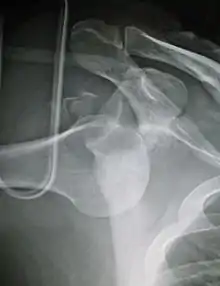

X-ray at left shows anterior dislocation in a young man. X-ray at right shows the same shoulder after reduction and internal rotation, revealing a Bankart lesion and a Hill-Sachs lesion.

In over 95% of shoulder dislocations, the humerus is displaced anteriorly.[6] In most of those, the head of the humerus comes to rest under the coracoid process, referred to as sub-coracoid dislocation. Sub-glenoid, subclavicular, and, very rarely, intrathoracic or retroperitoneal dislocations may also occur.[7]

Anterior dislocations are usually caused by a direct blow to, or fall on, an outstretched arm. The person typically holds his/her arm externally rotated and slightly abducted.

A Hill–Sachs lesion is an impaction of the head of the humerus left by the glenoid rim during dislocation.[5] Hill-Sachs deformities occur in 35–40% of anterior dislocations. They can be seen on a front-facing X-ray when the arm is in internal rotation.[8] Bankart lesions are disruptions of the glenoid labrum with or without an avulsion of bone fragment.